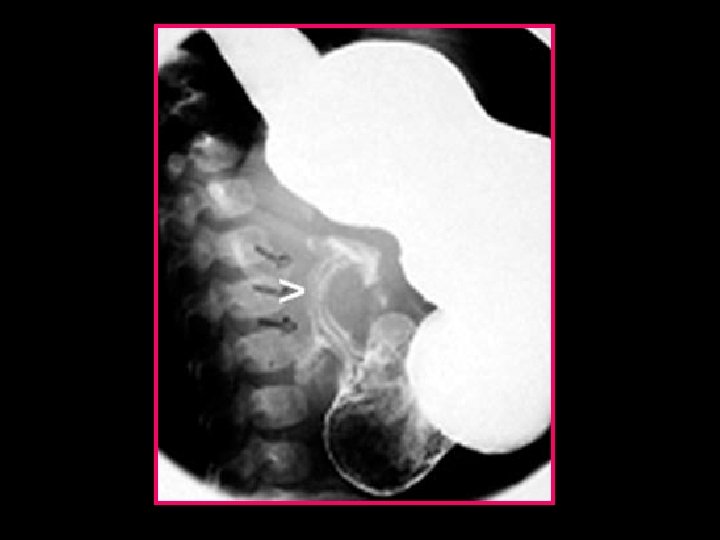

VI- RADIOLOGIE ASP - dilatation et stase gastrique - rareté des clartés digestives - Rx normale n’élimine pas le Diagnostic

Estomac de stase Rareté des clartés digestives

TOGD • N’est pas systématique : - symptomatologie atypique - échographie non concluante • Signes indirects : - dilatation et stase gastrique - estomac de lutte - retard de passage transpylorique • Signes directs ( pathognomoniques) : - défilé pylorique - image en parenthèses